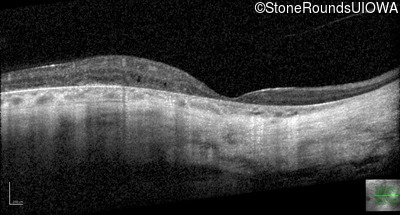

Optical Coherence Tomography - Right - 20/50 -1 sc

Exemplar / OCT Stack